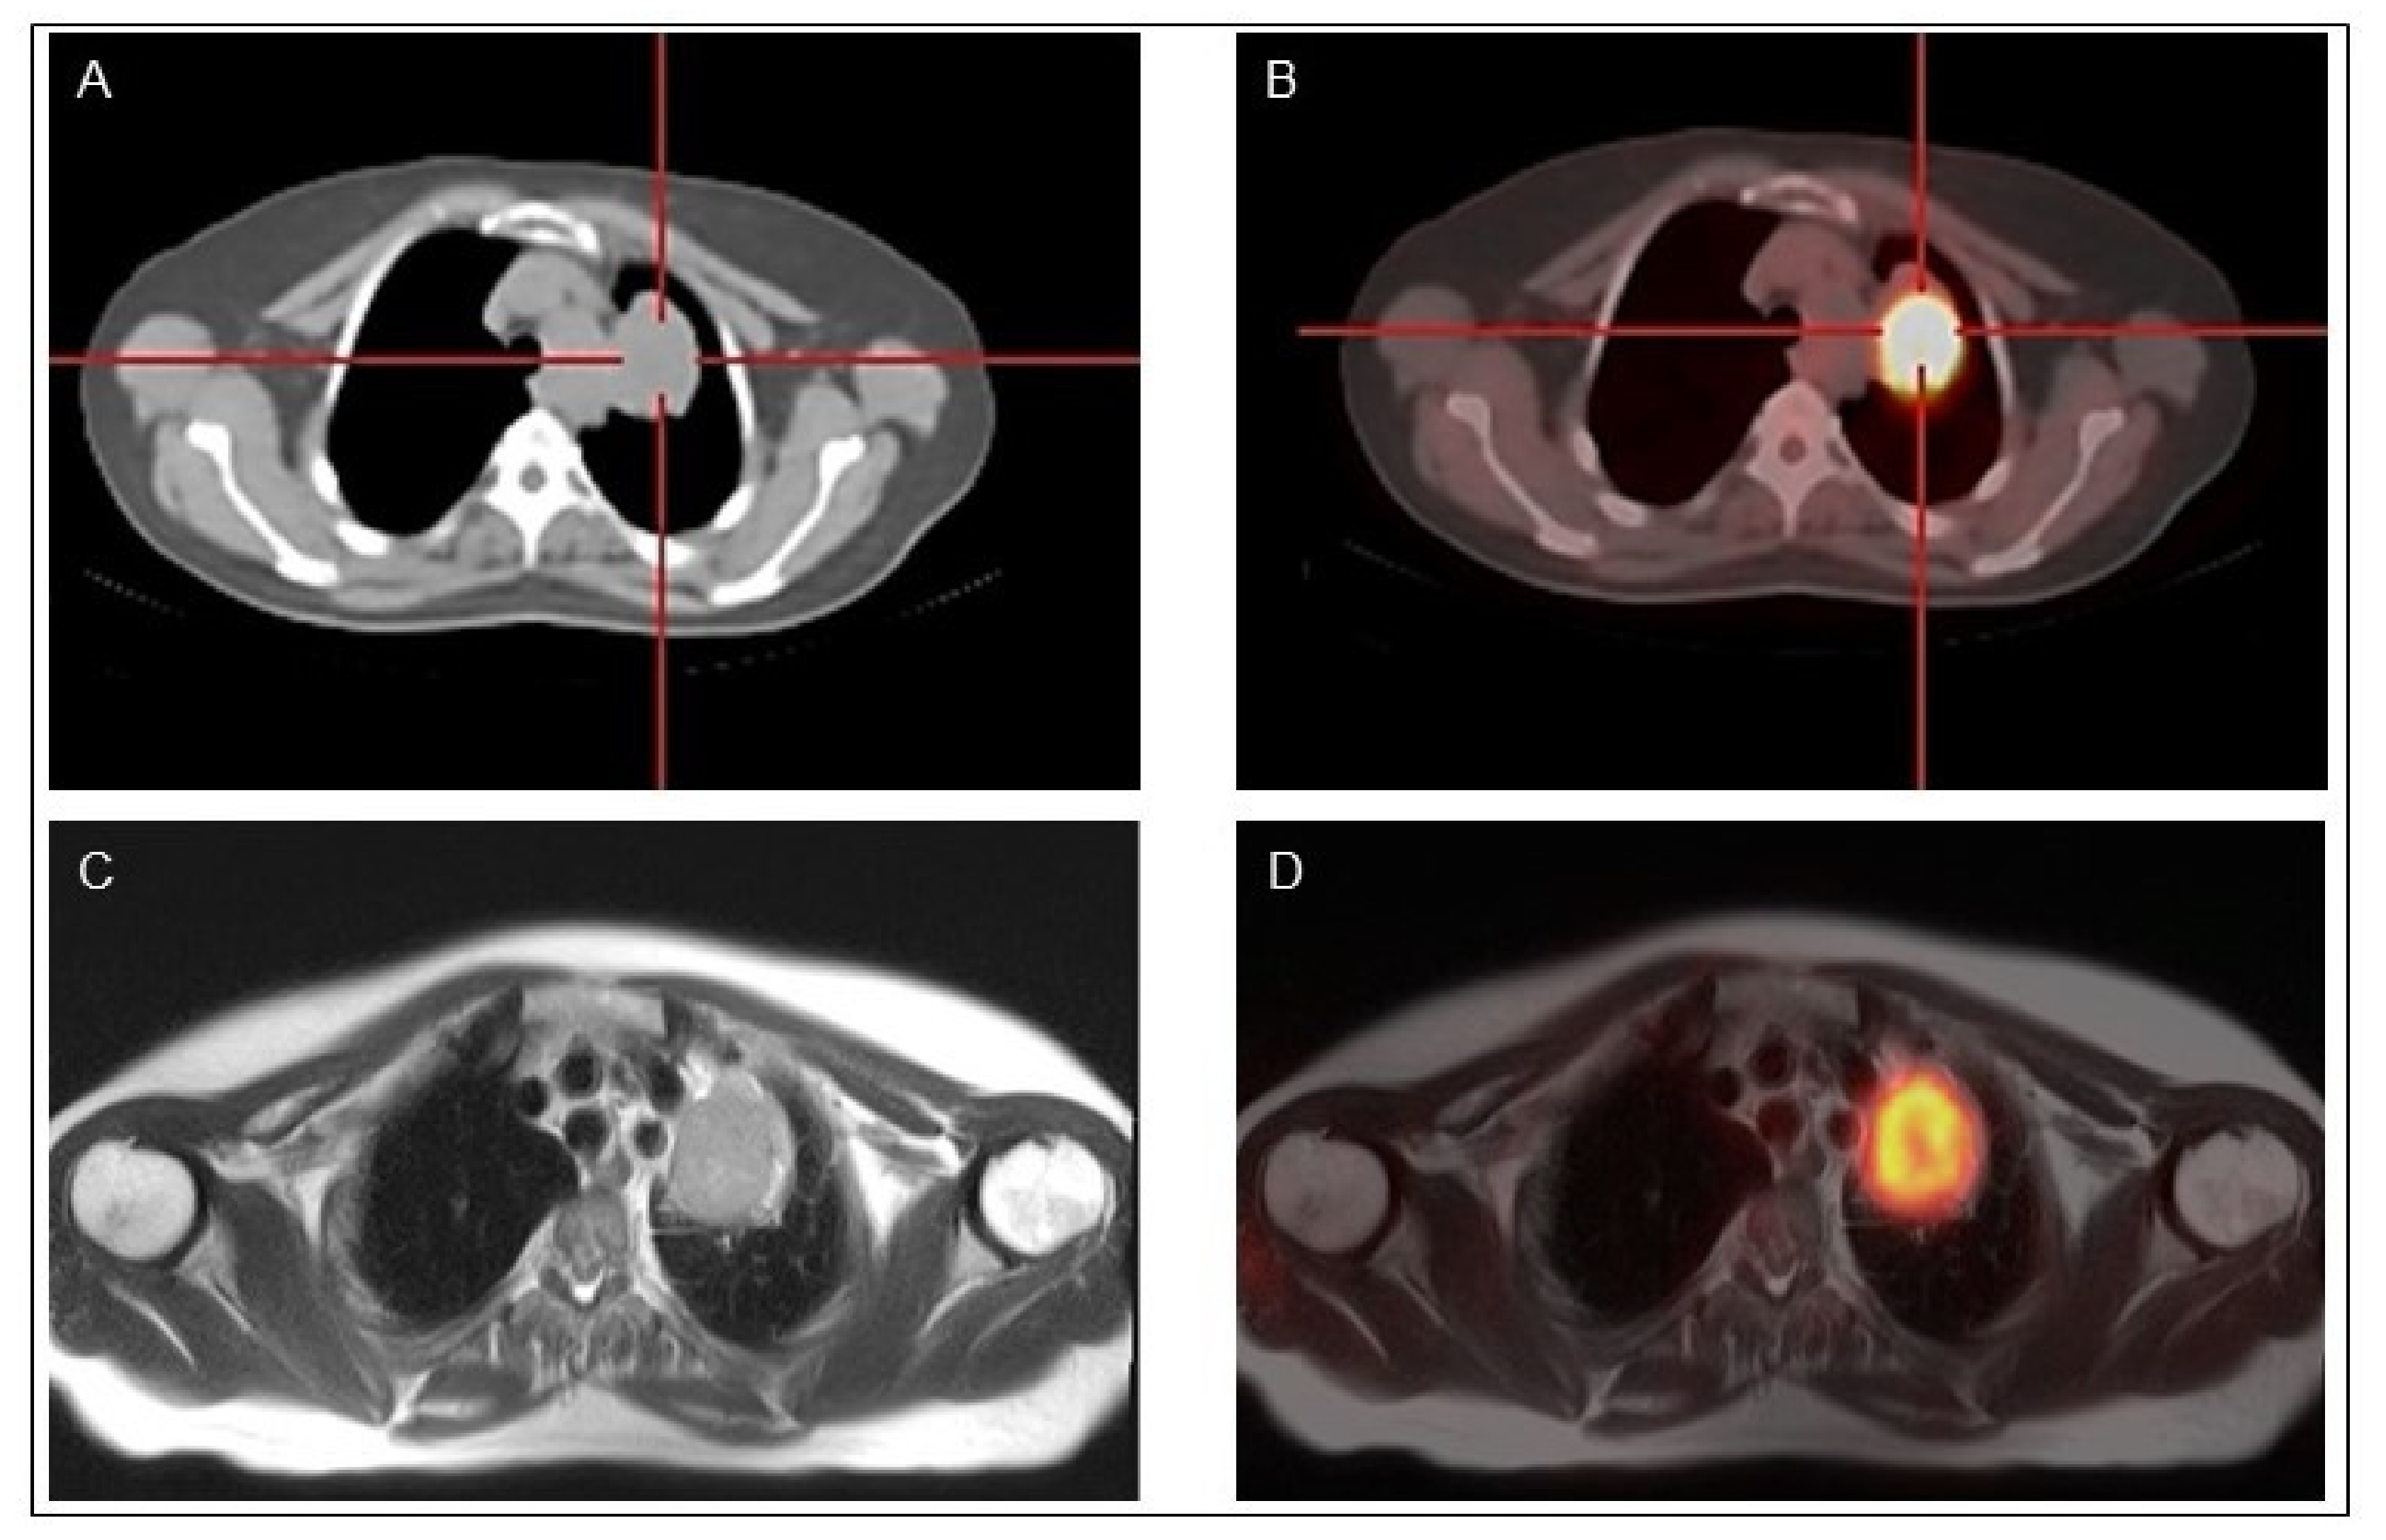

4.2. PET/MR

- Vrachimis, A.; Burg, M.C.; Wenning, C.; Allkemper, T.; Weckesser, M.; Schäfers, M.; Stegger, L. [(18)F]FDG PET/CT outperforms [(18)F]FDG PET/MRI in differentiated thyroid cancer. Eur. J. Nucl. Med. Mol. Imaging 2016, 43, 212–220. [Google Scholar] [CrossRef] [PubMed]

- Klain, M.; Nappi, C.; Nicolai, E.; Romeo, V.; Piscopo, L.; Giordano, A.; Gaudieri, V.; Zampella, E.; Pace, L.; Carlo, C.; et al. Comparison of simultaneous 18F-2-[18F] FDG PET/MR and PET/CT in the follow-up of patients with differentiated thyroid cancer. Eur. J. Nucl. Med. Mol. Imaging 2020, 47, 3066–3073. [Google Scholar] [CrossRef]